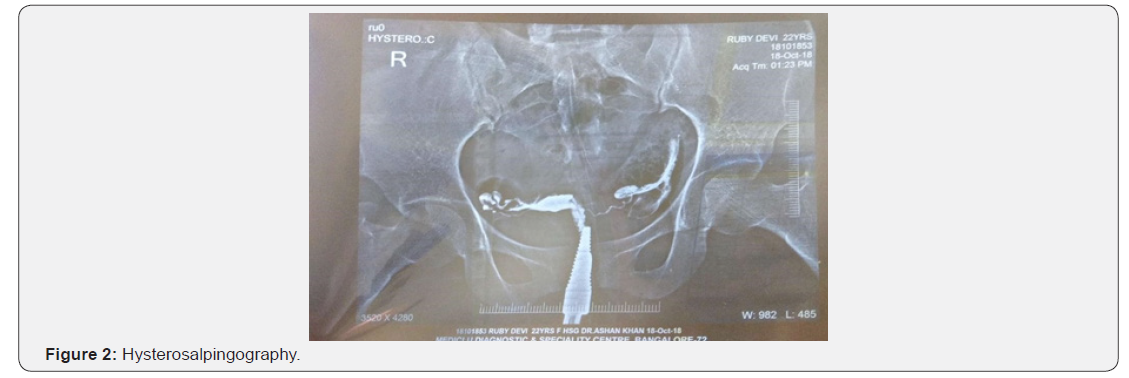

On examination, her vitals were stable, breast revealed no tenderness or palpable lump, bilateral chest was clear, normal vesicular breathing sound & S1 & S2 were audible with no murmur and per abdomen was soft and nontender. Per vaginal examination revealed anteverted, normal sized, mobile and firm uterus with no fornicial tenderness. Investigation recommended were semen analysis for male partner and CBC, ABO Rh typing, CUE, FBS, AMH, D2 S. FSH, S. LH, PRL, TSH levels & TVS for antral follicle count and HSG on D9 of cycle for female partner. Husband semen analysis was normal with 104 million sperm count, normal morphology and good motility, while female partner had B positive blood group, Hb% 12.5gm/dl, FBS 88mg/dl, AMH 2ng/ ml & her hormonal profile was FSH 7.8IU/L, LH 2.45IU/L, PRL 15ng/ml, TSH 2.3mU/L on D2 of cycle. HSG showed normal uterine cavity and fallopian tube with bilateral spillage in peritoneal cavity. TVS on D2 of cycle showed good antral follicle count without any pelvic pathology

Baikh asgand (Withania somnifera Dunal), baikh piyabansa (Barleria prionitis Linn), gule dhawa (Anogeissus latifolia) and gule nilofar (Nymphaea alba Linn) are muqawwi rahim, moaene hamal and increases the madda manwia; hence useful in uqr as it induces the ovulation [4,7]. Asgand contains alkaloids and steroidal lactones are the main constituents, gul dhawa consist of (saponins, tannin quercetin, phenolic compounds), gule nilofar is rich in alkaloids, whereas piyabansa contain anthraquinone pigmented, barleriaquinone, all are responsible for phytoandrogen- oogenic, antistress and insulin sensitising activities [8-10]. For detection of ovulation, serial follicular monitoring is the gold standard method which was not done in this case as she was not affordable, but the confirmatory test is pregnancy which was positive in this case. Unani medicine helped the patient to conceive within two cycles of treatment, without any observable side effects. Further comparative studies, with serial follicular monitoring & mid luteal serum progesterone may be helpful to establish the effectiveness of Unani medicines in such cases (Figure 1-3).